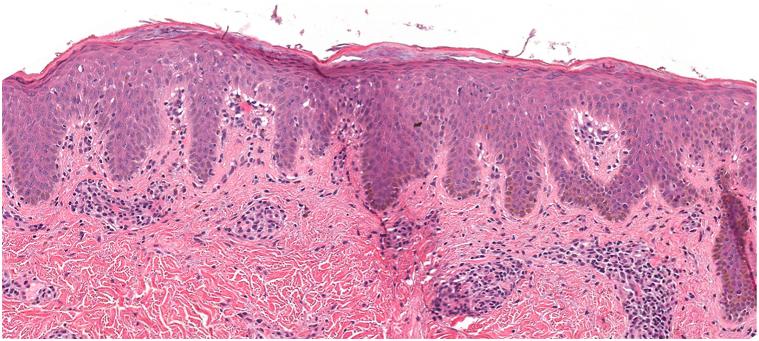

Dupilumab for the treatment of pityriasis lichenoides chronica.

JAAD Case Rep. 2024 May 30;50:9-11. doi: 10.1016/j.jdcr.2024.05.021. eCollection 2024 Aug.

Dupilumab for the treatment of pityriasis lichenoides chronica.度普利尤单抗治疗慢性苔藓样糠疹。